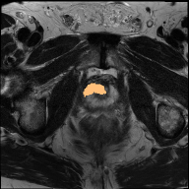

PROMISE12 Dataset: PROMISE12 dataset [18] consists of 50 transverse T2-weighted MRI scans. Following the data split in Liu et al. [19], there are 35, 5, and 10 scans for training, validation, and testing.

Some qualitative segmentation results on the three datasets are shown in Fig. 4, where we can observe that the proposed DSPIF achieves accurate segmentation results.

Results on PROMISE12 Dataset: In Tab. 3, based on MCNet baseline, the proposed method achieves 24.0% Dice and 23.78% JAC (resp., 7.86% Dice and 8.16% JAC) improvement under the setting of using 10% (resp. 20%) labeled data. Compared with state-of-the-art method BCP [3], the proposed method built on CPS [10] achieves an improvement of 3.89% (resp. 3.73%) Dice when using 10% (resp. 20%) labeled data.